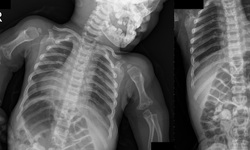

Thuốc mới - 22/11/2021 15:30SKĐS – Hội chứng lùn achondroplasia là một rối loạn di truyền bẩm sinh. Trẻ mắc hội chứng lùn có chân tay ngắn trong khi ngực phát triển bình thường.